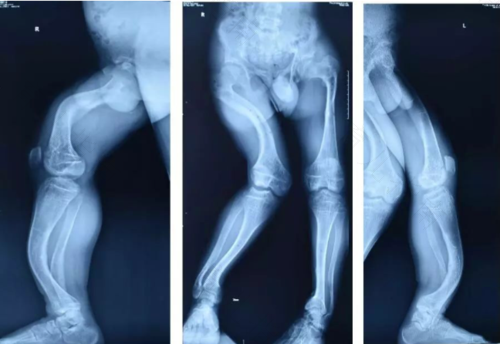

遗传病有很多种,一定要知道是什么原因导致的遗传病才能够更好的治疗。而患有抗维生素d佝偻病的人,骨骼的发育很奇怪,而且还有O型腿和走路不正常表现。那么抗x维生素d佝偻病到底是什么呢?

抗维生素D佝偻病是显性的伴随x染色体的遗传病,如果有这种遗传病的人,肾小管是很难吸收得到磷元素的,而且检查的时候还会发现血磷非常低。其次,这种遗传病对一般小剂量的维生素d是没有效果的,不能够正常的从肠道里面吸收钙元素的。